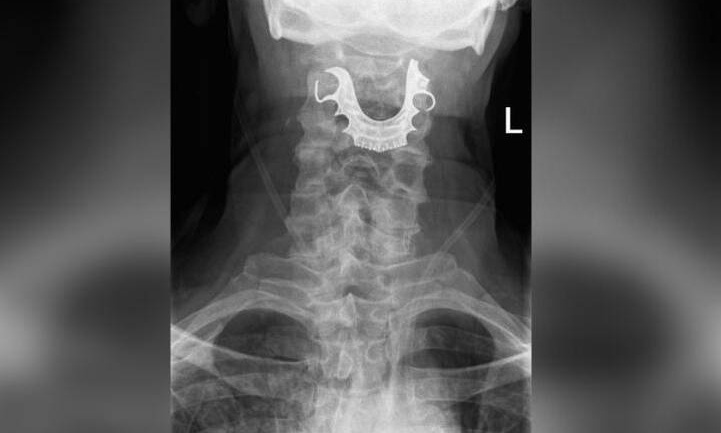

Μία… μασέλα κολλημένη στον λαιμό του είχε επί οκτώ ημέρες ένας 72χρονος, μετά από χειρουργική επέμβαση.

Ο άνδρας από την Αγγλία, υποβλήθηκε σε χειρουργείο για την αφαίρεση ενός ακίνδυνου όγκου, αλλά οι γιατροί παρέλειψαν να του βγάλουν τη μασέλα πριν την επέμβαση.

Έξι μέρες μετά, επέστρεψε στο νοσοκομείο, διαμαρτυρόμενος για αίμα στο στόμα του και δυσκολία στην αναπνοή και την κατάποση.